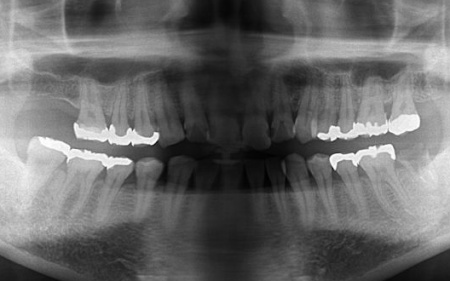

拝見したところ、複数の歯に虫歯が見られました。また、過去に治療した詰め物や被せ物が合わなくなっている部分や、歯が欠損している部位もあります。

・右上奥歯

一番奥の歯が欠損し、その手前の歯は詰め物の内部で虫歯が進行しています。

・右下奥歯3本

噛む面や歯間に虫歯が見られ、歯が欠けている部分もあります。

・左上奥歯

一番奥の歯は、詰め物が合っていませんでした。また、詰め物が外れたままの歯もあります。

・左上前歯2本

虫歯や、被せ物の不具合が見られました。

・左下奥歯

一番奥の歯は虫歯が深くまで進行しており、歯の温存が難しい状態でした。さらに、その手前の歯2本は少し欠けています。

・前歯の噛み合わせ

下前歯が上前歯より前に出ている「反対咬合(こうごう)」で、将来的に歯や顎への負担が生じるリスクがあります。

・インプラント治療

保存が難しい左下奥歯(第2大臼歯)と、すでに欠損していた右上の部位については、インプラント治療を行います。インプラント治療とは、顎の骨に人工歯根を埋め込み、そこに人工歯を取り付ける治療方法です。

右上の欠損部位についても、同じくインプラント治療を実施しています。